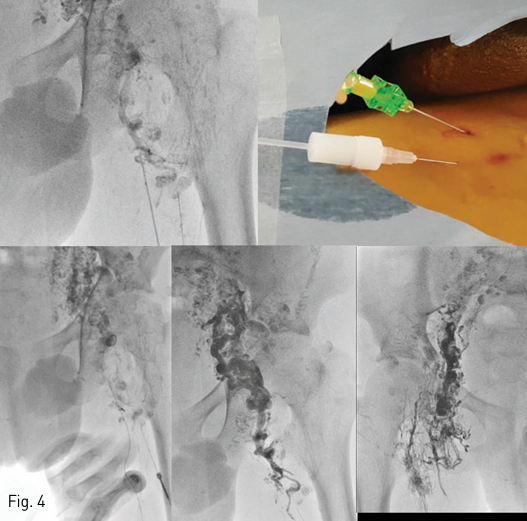

Fig 4

(Top left) A prominent lymphatic vessel (arrow) in left thigh area was directly punctured using 21 gauge needle under the fluoroscopic guidance. (Top right) Chylous fluid was gushed out from the needle immediately after the puncture of the vessel. (Bottom) A microwire (0.016 inch, Meister, Asahi Medical) and a microcatheter (2.0 Fr, Progreat alpha, Terumo) were advanced along the vessel up to the pelvis level. Then, the lymphatic vessels in the pelvic and inguinal area were embolized using 1:5 NBCA:Lipiodol mixture to occlude the reflux of the chylous fluid from small bowel to the scrotal skin. The same procedure was performed for the right side.

소장으로부터의 유미성 림프액 역류를 막기 위해서 서혜부 및 허벅지 안쪽으로 향하는 림프관에 대한 색전 시술을 계획하였다. 서혜부 림프절 경유 리피오돌 림프 조영술을 다시 시행하여 양측의 비대된 서혜부의 림프관을 조영하고 이를 투시 유도하에 21 gauge 5 cm 바늘(Cook, Bloomington, IN)로 직접 천자하여 유미 림프액의 유출을 확인하였다. Meister 미세 유도 철사 (0.016 inch, Asahi Medical, Japan)와 Progreat alpha 미세 도관 (2.0 Fr, Terumo, Japan)을 림프관에 삽입하고 골반과의 경계 부위까지 전진시킨 다음 접착체 [N-butyl cyanoacrylate (Histoacryl, B Braun)와 리피오돌 (Lipiodol Ultrafluid, Guerbet, France)의 1:5 혼합물]을 이용하여 색전술을 시행하였다(Fig. 4).